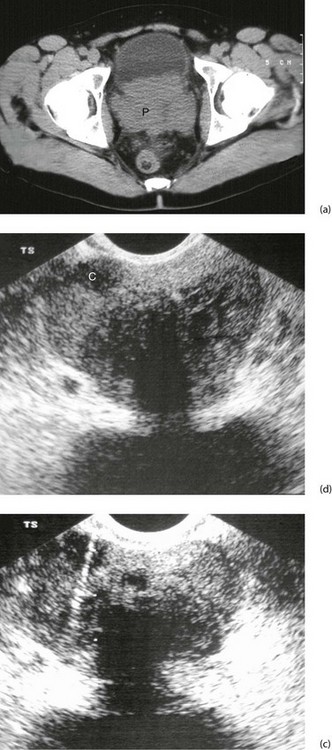

Fig. 35.7 Carcinoma of the prostate

(a) CT scan showing a large carcinoma of the prostate P invading extensively into the bladder anteriorly and posteriorly towards the rectum. This was a late and aggressive form of the disease and the patient lived less than 1 year. (b) and (c) Ultrasound guided biopsy. (b) Transrectal ultrasound scan of prostate showing a small cancer C within the peripheral zone and an acoustic shadow beyond it. The larger central zone is enlarged by benign hypertrophy. (c) After transrectal biopsy. The white line represents bubbles of air left after successful needle biopsy of the tumour